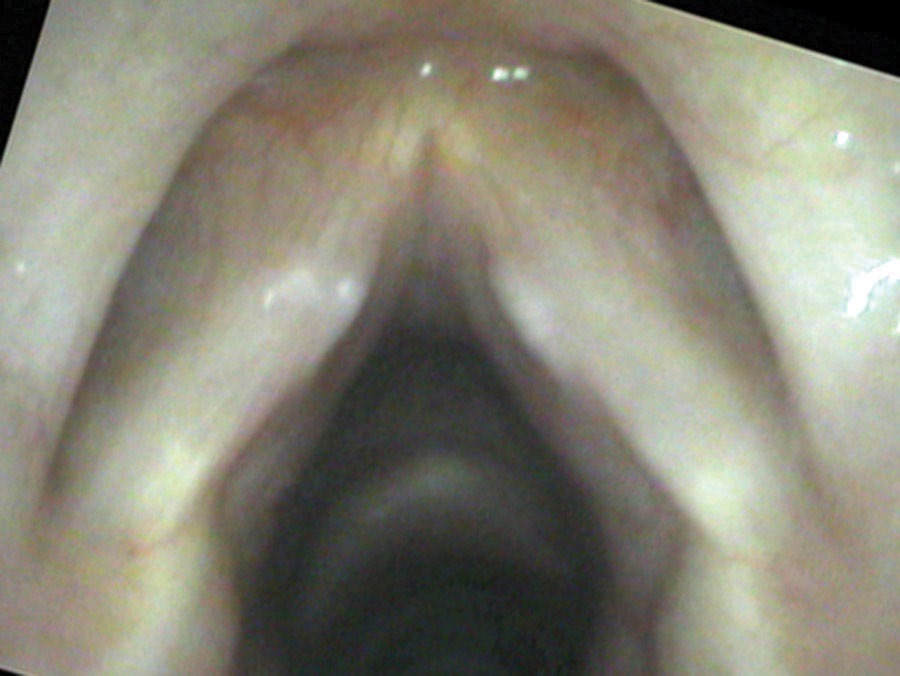

When the vocal cords are brought into a closed position, the opposing swellings touch one another before the cords completely line up, creating a gap in front of and behind the swellings through which air leaks. Because they touch, there is a dampening of vibrations that prevents soft phonation. Think of trying to play the violin while someone lightly touches the string: it requires more force with the bow to set the string vibrating. The lungs must push more air to start vibrations, and there will be audible onset delays at the start of soft phonation.

With time, the individual develops compensation — holding the vocal cords slightly apart to keep the bumps from touching. This requires simultaneous activation of the LCA muscle (which brings the cords together) and the PCA muscle (which keeps them apart). Two opposing muscles competing against one another produce vocal discomfort, pain, and fatigue.